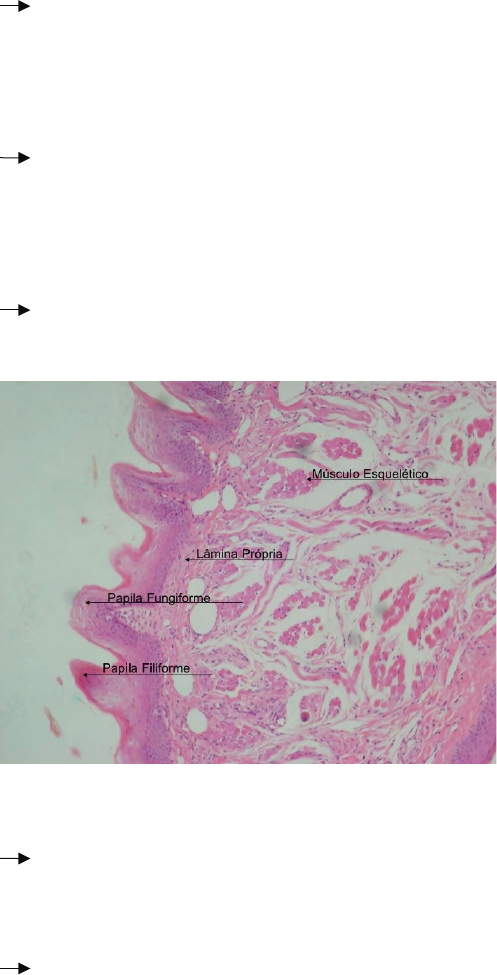

A língua é uma massa de músculo estriado esquelético revestida por uma camada mucosa cuja estrutura varia de acordo com a região

Musculo estriado da língua esta disposto em feixes, possibilitando enorme flexibilidade e precisão nos movimentos da língua.

são elevações do epitélio oral e lâmina própria

que assumem diversas formas e funções.

1. Papilas Filiformes

- Menores e mais numerosas nos humanos, estão sobre toda superfície dorsal da língua, possuem função de fricção.

- Cônicas e alongadas de tecido conjuntivo, cobertas por epitélio estratificado pavimentoso queratinizado e não possuem botões degustativos.

2. Papilas Fungiformes

- Formato de cogumelos, mais numerosas na ponta da língua, contem poucos botões degustativos.

- Menos queratinizado e maior vascularização